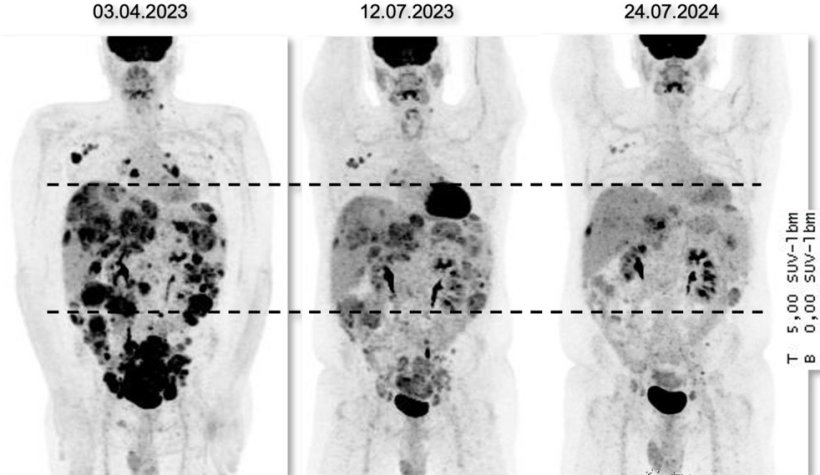

Bildquelle: NCT Heidelberg; adaptiert von: Renner M, Oleś M, Paramasivam N et al., Nature Communications 2026 (CC BY 4.0)

Bemerkenswert ist, dass die Forschenden im Tumorgewebe häufig Proteine nachweisen konnten, die mit neuartigen, zielgerichteten Therapien adressiert werden können, insbesondere mit Antikörper-Wirkstoff-Konjugaten (ADC) oder mit therapeutischen Immunzellen, den CAR-T-Zellen. Mit einem ADC der jüngsten Generation, Trastuzumab Deruxtecan, wurde bei zwei Betroffenen eine ungewöhnlich lange anhaltende Tumorkontrolle erreicht, in einem Fall über zwei Jahre. Zusätzlich ergab die Studie, dass die Tumoren in acht von 30 Fällen erst durch die molekulare Analyse vollkommen richtig diagnostiziert werden konnten.